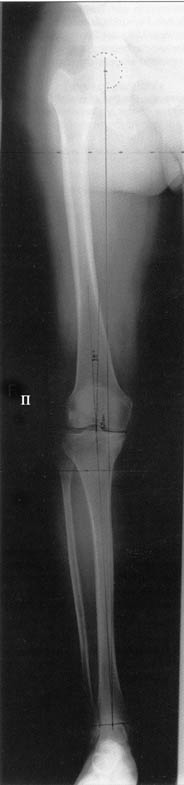

Большая просьба прокомментировать прилагавшиеся снимки. Видно, что сделано что-то красивое, но не совсем понятно, по какому поводу, как рассчитывалась коррекция, и что именно сделано.

Поделитесь, пожалуйста, опытом, как Вам удается выполнять такие качественные рентгеновские снимки всей ноги полностью? На трех кассетах одновременно? Стыки кассет обычно <крадут> 1-2 см изображения. На снимке Вашего пациента <украденных> участков нет!

Качественные под нагрузочные рентгеновские снимки, получаются благодаря современному рентгеновскому оборудованию фирмы SIEMENS, (подробности могу уточнить у рентгенологов), а качественно стыковать (прозрачный скотч) научились с годами, но это для публикаций, для работы достаточно скрепить степлером по анатомическим осям с учетом толщины диафизов и грамотно расчертить. Пособие с удовольствием отправлю.